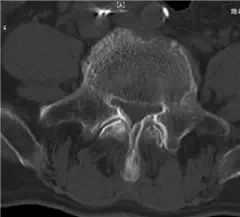

CT骨窗L3-4、L4-5